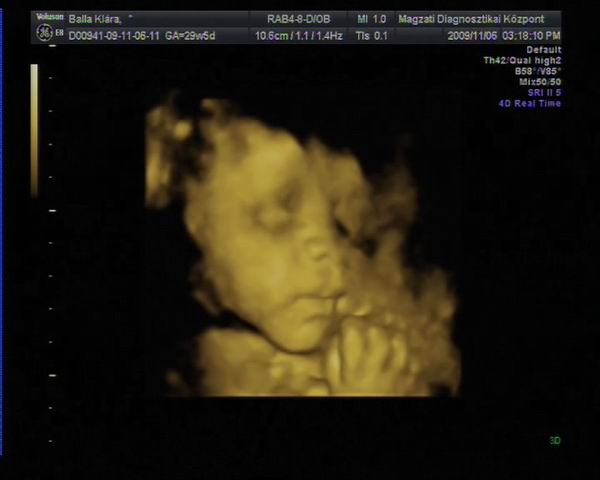

Athena, Jutka. Nilszi-nek igaza van abban, hogy sokszor nem mérnek pontosan az UH-k alkalmával. Misem bizonyítja ezt jobban , mint az én esetem. Szerdán este a rendeléses Uh-n , ahol elég lelkiismeretesen mért a szonográfusnő, ott a picur méretét: 1518g-ra becsülték ( kicsit meg is ijedtem!) A pocakja szép nagy volt AC:255mm a combcsontja, amire kétszer is rámért FL:53mm, BPD( fejátmérő):75mm HC ( fejkörfogat):266mm.

Másnap reggel mentem 4D UH-ra, ahol BPD: 72,6mm HC: 261,9mm AC: 220,2mm FL: 57,5mm becsült súly: 1108g.

Pedig ugyan arról a gyerekről van szó!!!! Nem hiszen, hogy lüktetne a pocakomban. :lol:

Hát ennyit a gépekről és a pontos méretekről!!!

Ráadásul képzeljétek hogy jártam a 4D UH-n. Zsomborka egyáltalán nem akarta megmutatni magát, nem fordult be a gerincem felé néz és annyira betakarta a karjával és a felhúzott lábacskáival magát, hogy semmit nem lehetett látni belőle. Hiába forogtam, mozgattuk a pocakom, fel sem ébredt és egyáltalán nem akart elmozdulni.

Egyetlen képet tudott csak készíteni a szonográfus, azt is csak a talpacskájáról. Nagyon csalódott voltam, mert ugye azt már tudtam, hogy egészséges nincs semmi baja, mert azt már előző nap megnézték, most csak őt szerettük volna látni. Így nagy nehezen kikönyörögtem, hogy nem jöhetnék-e vissza, hátha fordul egy kicsit. Kora délutánra kaptam még egy időpontot. Persze mondanom sem kell, hogy otthon még bukfenceztem is, hogy egy kicsit elforduljon, csokit ettem, kávét ittam ( pedig soha nem iszom )

A babóca mégsem akart elmozdulni, már majdnem azt mondta a szonográfus, hogy csinál egy képet, de hagyjuk a DVD-t mert most sem látszik semmi, mikor egyszer csak mintha halotta volna Zsimbi mégiscsak fordult egy kicsit, hogy végre szülei megcsodálhassák. Persze a kép szemcsés volt és még így is betakart a kis kezecskéje egy kicsit, de mi olyan boldogok voltunk, hogy végre látunk belőle valamit, hogy madarat lehetett volna fogatni velünk. Sőt még ásított is egyet, biztos érezte, mekkora a sikere, annak, ha kicsit produkálja magát. Így végre meg lett a várva várt DVD. Sajnos képet nem tudok róla berakni, mert a laptop-om nem szereti ezt a DVD-t és nem akarja elindítani, így csak a lejátszónkon tudom megnézni, de ott nem tudok képeket kivágni. Így csak egy képet tudok bescannel-ni, amit az Uh-osok nyomtattak ki fekete fehérben.

Kép Zsomborka 28+4

Kép Zsimbi talpacska